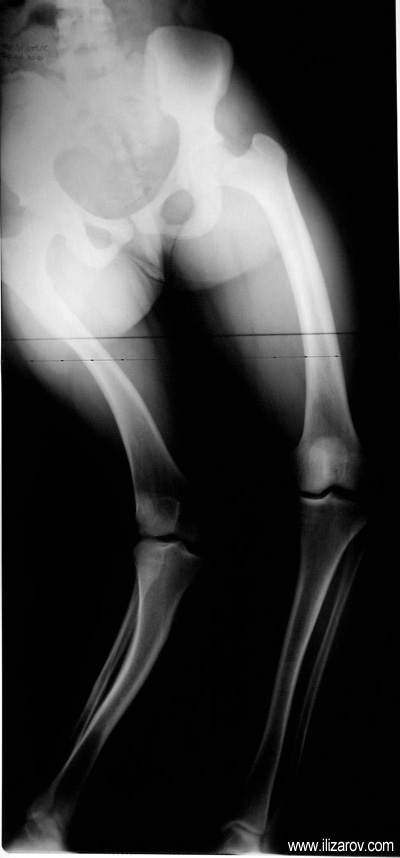

In hypophosohatemic rickets, abnormal bone findings become evident after 1 year of age; there are short stature and deformities around the knee (bilateral genu valgum or varum, tibial torsion, deformity at tibia and femur, ‘windswept’ deformity).

Because the deformity caused by hypophosphatemic rickets is very close to the growth plate, a significant deformity and malalignment occurs. For that reason, more than one deformity centers (CORA) are found at preoperative evaluation, and osteotomy at more than one level is required to correct the deformity. The most frequently used methods to correct the deformity are acute or gradual deformity correction using the Ilizarov method or unilateral external fixator. In the ‘fixator assisted nailing’ technique, which is applied in our department, the deformity is corrected in an acute fashion with the help of an external fixator, and the extremity is stabilized by an intramedullaru nail. The external fixator is removed before the end of the surgery if no gradual lengthening is planned postoperatively. If lengthening (over nail) is planned, the fixator is removed after the completion of the lengthening procedure. As a result, the risk of pin tract infection is eliminated, correction loss and relapsing of the deformity (which are important problems in the treatment of hypophosphatemic rickets) are avoided, eary motion and full weight bearing are allowed, and comfortability of the patient is improved because the duration with external fixator is decreased.

Case 1